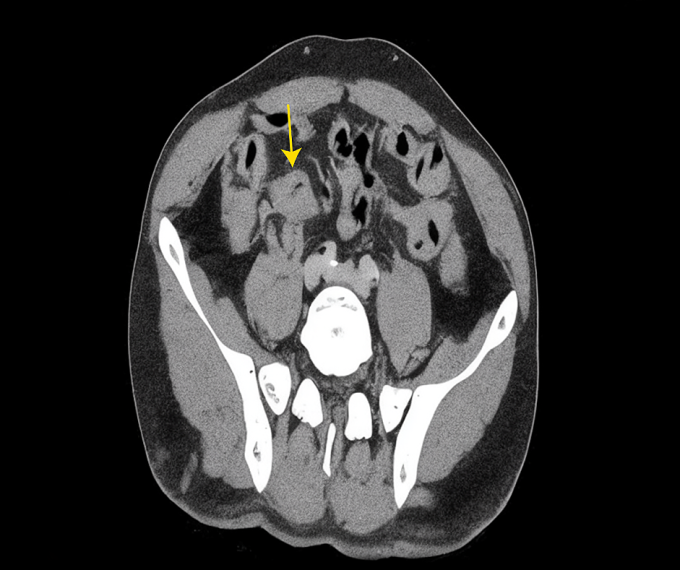

Chụp CT cho thấy khối u ở gan (mũi tên vàng). Ảnh: Bệnh viện Đa khoa Tâm Anh

Giải phẫu bệnh xác định ung thư biểu mô tuyến xâm nhập, biệt hóa vừa. Tiến sĩ, bác sĩ Phạm Công Khánh, Trưởng khoa Gan – Mật – Tụy, Trung tâm Nội soi và Phẫu thuật Nội soi Tiêu hóa, chẩn đoán ông anh Ngọc ung thư manh tràng – đại tràng lên giai đoạn muộn, di căn gan tại hạ phân thùy ba.

Theo bác sĩ Khánh, thông thường ung thư đại trực tràng đã di căn gan ít có khả năng phẫu thuật. Tuy nhiên, trường hợp này khối u gan di căn khu trú ở thùy trái gan nên vẫn có thể cắt bỏ hoàn toàn. “Nếu phẫu thuật, tỷ lệ sống sau 5 năm của bệnh nhân có thể 40-60%”, bác sĩ Khánh nói.